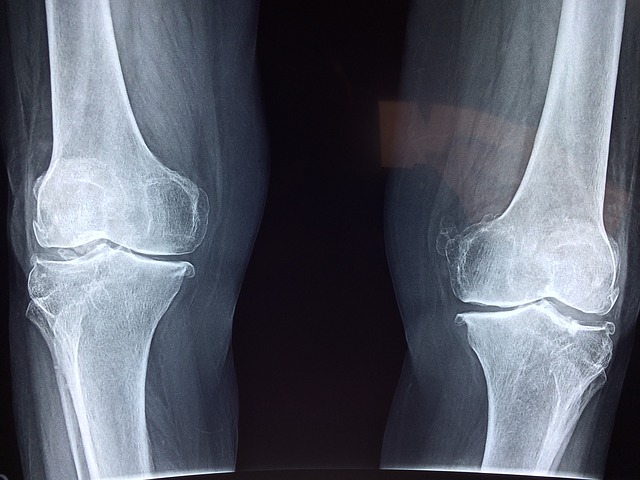

무릎관절염이란 골관절염의 범주 안에 속하는 개념으로 무릎에 나타나는 골관절염이라고 보시면됩니다.

1) 무릎에서 뼈와 뼈가 부딪히는 소리가 나면서 삐걱거리는 느낌이 든다.

무릎을 폈다가 구부릴 때 "딱딱" 하는 뼈와 뼈가 부딪히는 소리가 나면서 삐걱거리는 느낌이 드는 증상이 있습니다.

이것은 연골의 일부를 잃어서 나타나는 증상이라고 보시면 됩니다.

연골을 잃거나 손상이되면 관절이 움직일 때 마찰이 되어 뼈 부딪힘 현상이 나타납니다.